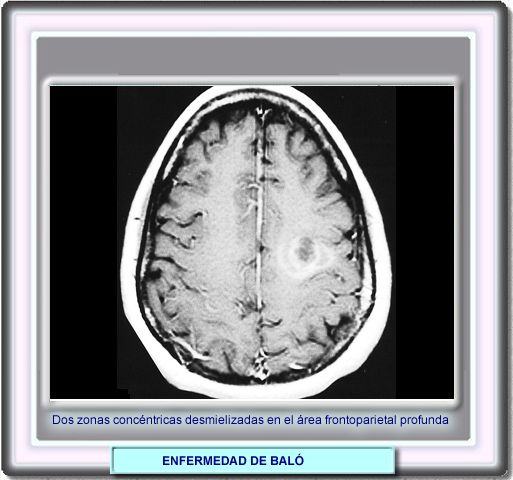

La

lesión puede observarse mejor mediante la resonancia con contraste

de gadolinio en T1. Se los círculos concéntricos representan

dos zonas de desmielinización activa. También se observa un

aumento de la permeabilidad de barrera hematoencefálica.